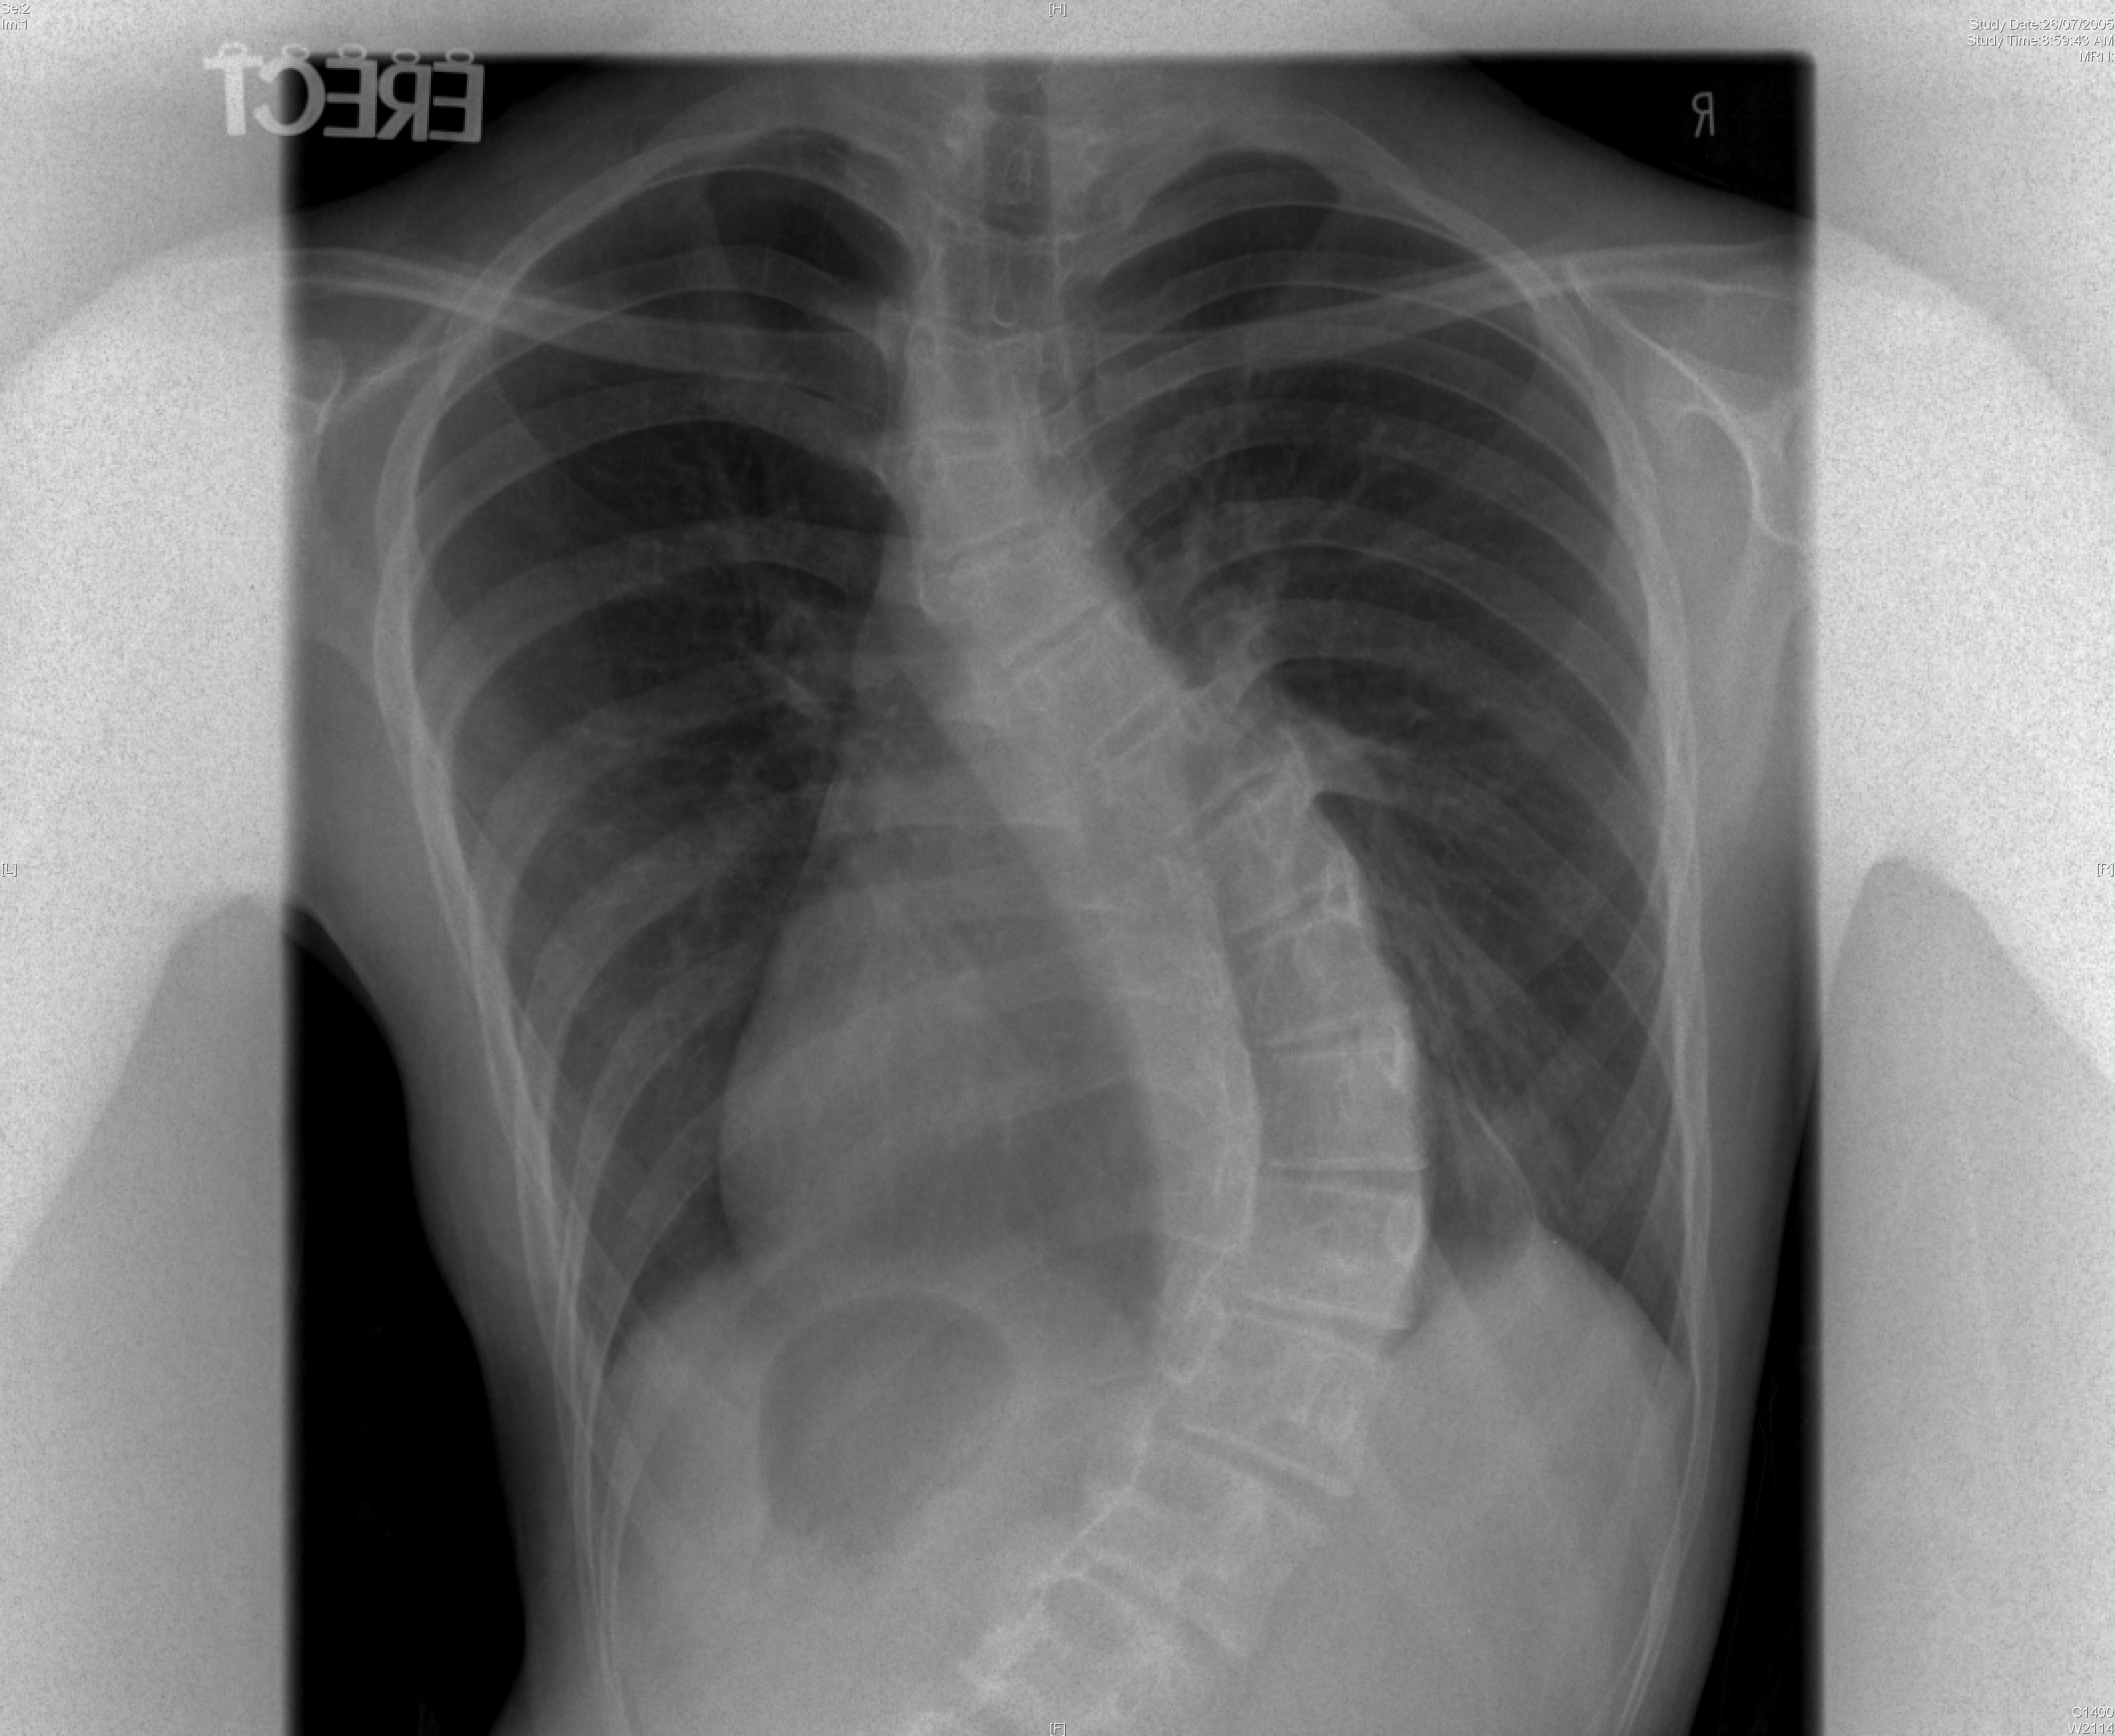

Currently artificial disc replacement can be used for the lumbar or the cervical spine. Many different models have been developed. The majority consists of two metal plates that have teeth to anchor the implant onto the bone of the vertebral bodies. Between the two plates is a metal core or a plastic core made up of polyethylene that allows for motion. Figure 1 shows a lumbar artificial disc replacement. Figure 2 shows a cervical artificial disc replacement.

The technique to insert an artificial disc (whether in the neck or low back) is routine and safe. For the cervical spine it involves going from the front of the neck. For the lumbar spine, it involves going through the abdomen. The procedure begins by removing the gelatinous disc between the vertebrae. Once the disc is removed, two metal plates are pressed into the bony endplates above and below the space now vacated by the disc. Metal spikes hold these plates in place on the bone. Eventually bone will grow over and around the metal plates. In between the metal plates is a metal or plastic core made of a polyethylene. Figure 3 shows the artificial disc placed in the spine.